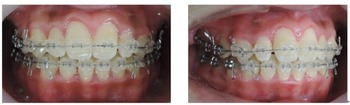

顎偏位の症例はMEAW(マルチループ)の得意としている症例です。

一般的な治療では非抜歯での治療は非常に困難な症例です。

治療は上顎から矯正装置を装着していきます。その後下顎の矯正装置を装着します。

この過程で歯並びが整いMEAW(マルチループ)を装着しやすくなります。

MEAW(マルチループ)を使用する事で顎偏位により左右の咬合高径(咬み合わせの高さ)の改善をしています。その治療により左右の顎のズレが改善されます。

顎偏位は上顎前突や下顎前突のように顎骨の前後のズレではなく左右のズレである為に歯を抜いて治療する事が出来ないストレートワイヤー法では治療が困難な症例です。

当院はMEAW(マルチループ)により効率的に治療を進めています。